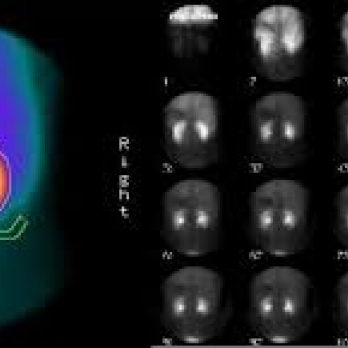

Renograma basal y post-captopril. 920808 . Se aplican dos dosis de DTPA Idime (2024)

IDIME. Instituto de Diagnóstico Médico. Código de Convenio : 8915

INCLUYE UNIDOSIS DTPA